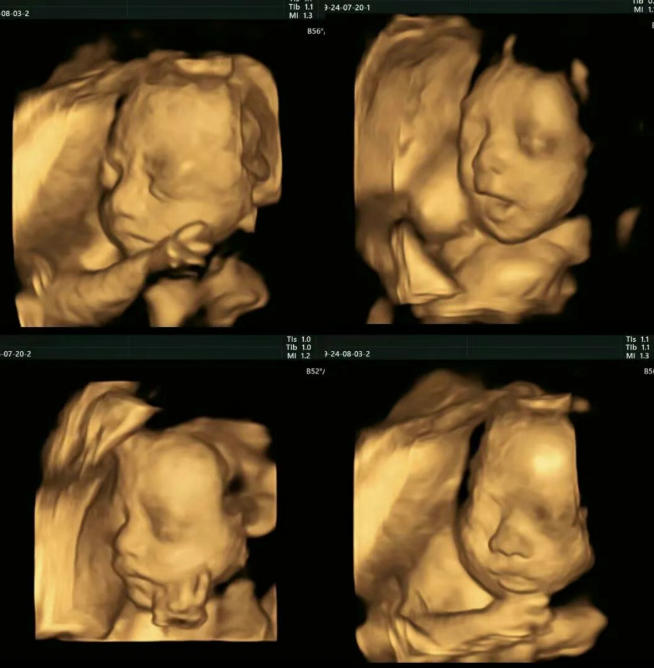

亲爱的准妈妈们,当您第一次在四维彩超屏幕上看到宝宝的小脸、清晰的五官,甚至撅起的小嘴时,是不是感觉心都化了?

很多妈妈都会忍不住拿着彩超照片反复看,猜测宝宝更像谁,却可能不知道,在您专注宝宝长相的同时,医生正专注地观察着更重要的事情。

事实上,四维彩超不仅是让您“提前见面”的温馨时刻,更是一次至关重要的系统性筛查。

四维彩超最佳检查时间一般为孕22-28周,此时宝宝结构发育较为完善,羊水量适中,成像最为清晰。这次检查不仅是与宝宝的第一次“见面”,更是一份重要的健康评估。艾玛四维彩超,有以下特点: